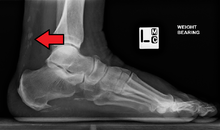

Gottron's papules. Erythematous to violaceous raised papules overlying the metacarpal

Gottron's papules. Erythematous plaques overlying the elbows in a patient with juvenile dermatomyositis. In some patients, small erythematous plaques may overly the extensor aspects of larger joints, such as the elbows, knees, and medial malleoli. This is considered to be an extended part of the spectrum of Gottron's papules. Note in Figure, a focal area of dystrophic calcification at the site of Gottron's papules, which is indicative of damage, as discussed below.